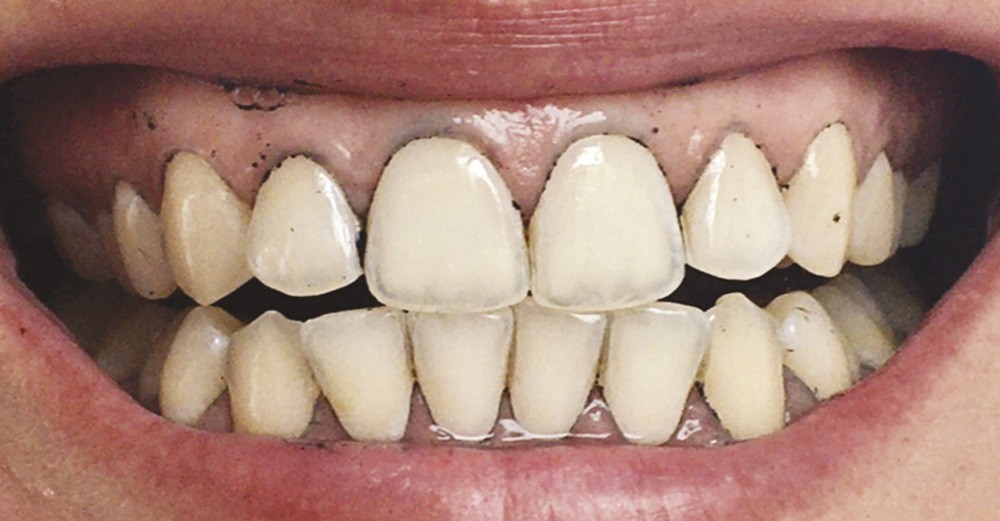

Les modifications hormonales à mettre en relation avec l’hygiène bucco-dentaire, les paramètres socio-économiques, l’âge précoce de la grossesse ainsi que l’augmentation du grignotage pourraient augmenter la prévalence des caries dentaires chez la femme enceinte. Ces patientes sont régulièrement sujettes à des envies multipliant le nombre de prises alimentaires souvent très riches en sucre. Ces apports sucrés, associés à la baisse du pH salivaire lors de la grossesse, entraînent un déséquilibre du cycle déminéralisation et de reminéralisation. Le risque carieux peut être augmenté, ainsi que la susceptibilité à l’érosion dentaire accrue par les vomissements et/ou les reflux gastro-œsophagiens [2]. L’action hormonale peut également avoir des répercussions sur les tissus parodontaux. La gingivite gravidique observée sur plus d’une femme enceinte sur deux, constitue une réponse inflammatoire de la gencive exacerbée par la présence de plaque bactérienne, et favorisée par l’augmentation des taux d’œstrogène et de progestérone [3] (fig. 1). 5 % des futures mères développeront un épulis, dont l’étiologie reste méconnue (fig. 2) [4].